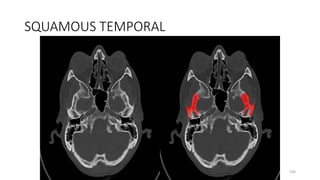

Temporal bone, tympanic

. Temporal bone, squamous part

SQUMOUS TEMPORAL

SQUAMOUS TEMPORAL

TEMPORAL BONE, SQUAMOUS PART